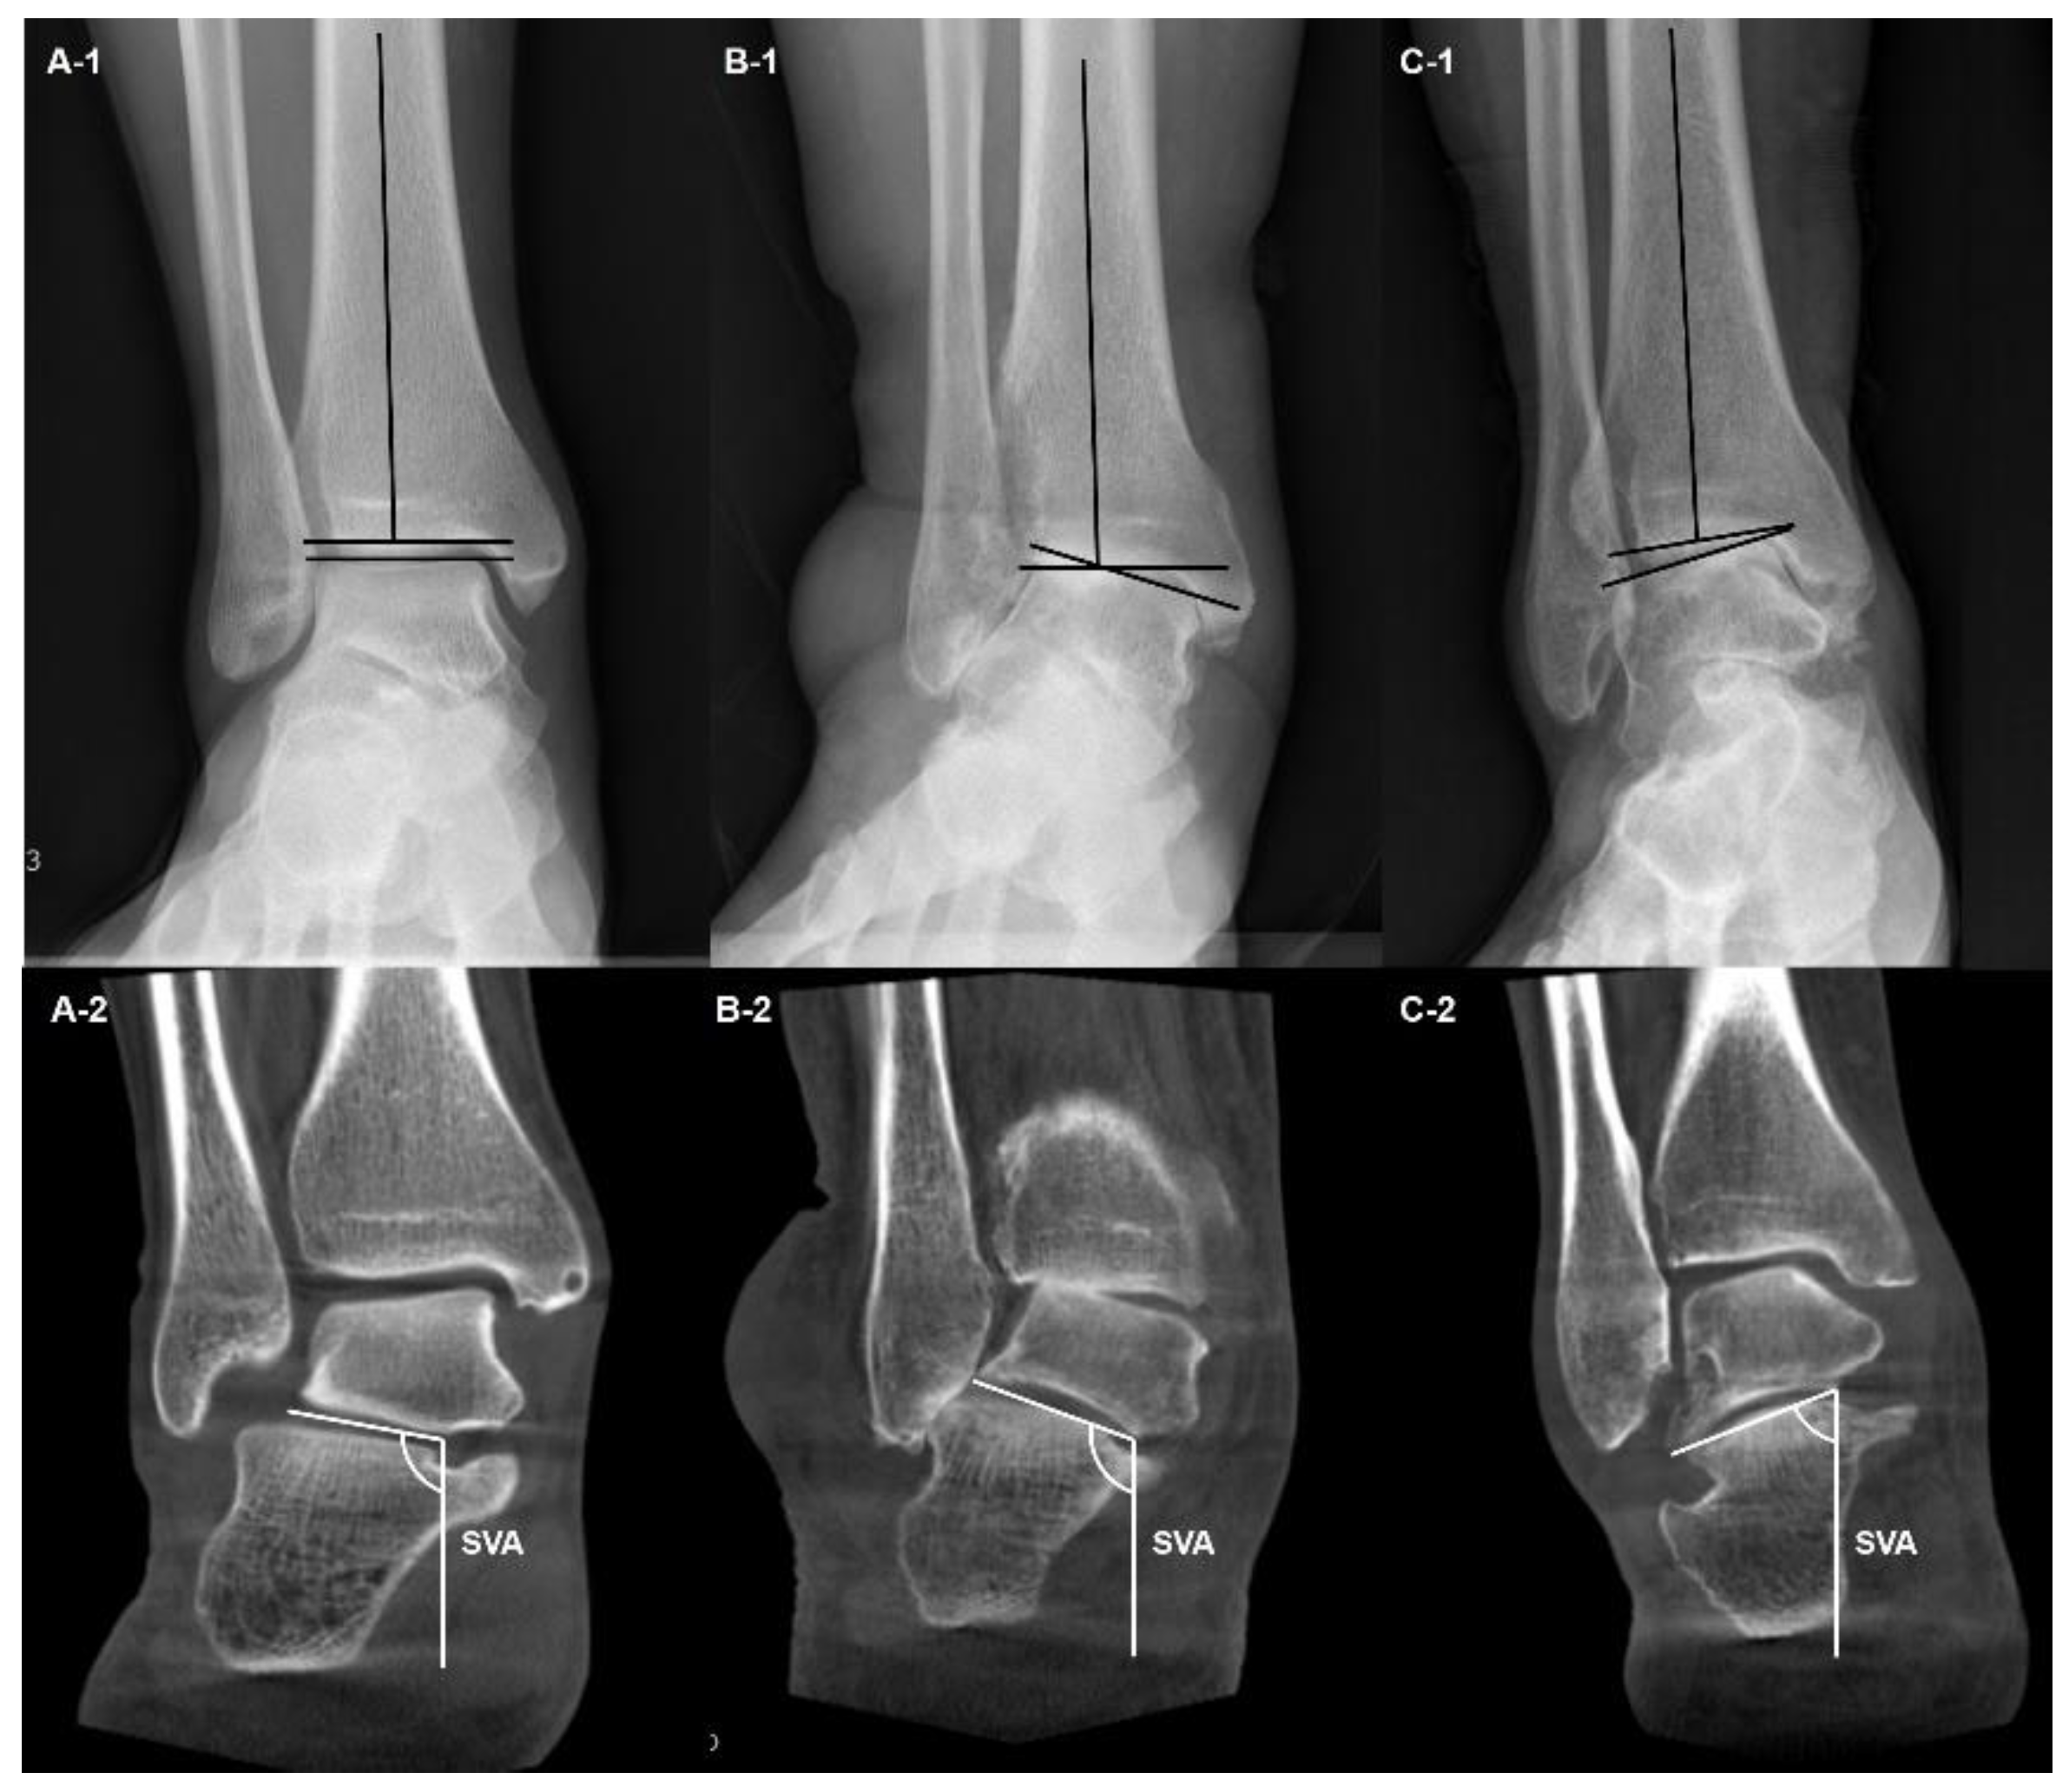

- Ankle Osteoarthritis

- Song, J.H.; Kang, C.; Kim, T.G.; Lee, G.S.; Lee, J.K.; Ahn, K.J.; Kim, D.H.; Lee, S.W. Perioperative axial loading computed tomography findings in varus ankle osteoarthritis: Effect of supramalleolar osteotomy on abnormal internal rotation of the talus. Foot Ankle Surg 2021, 27, 217–223. [Google Scholar] [CrossRef]

- Kim, J.B.; Yi, Y.; Kim, J.Y.; Cho, J.H.; Kwon, M.S.; Choi, S.H.; Lee, W.C. Weight-bearing computed tomography findings in varus ankle osteoarthritis: abnormal internal rotation of the talus in the axial plane. Skeletal Radiol 2017, 46, 1071–1080. [Google Scholar] [CrossRef]

- Kang, H.W.; Kim, D.Y.; Park, G.Y.; Lee, D.O.; Lee, D.Y. Coronal plane Calcaneal-Talar Orientation in Varus Ankle Osteoarthritis. Foot Ankle Int 2022, 43, 928–936. [Google Scholar] [CrossRef]